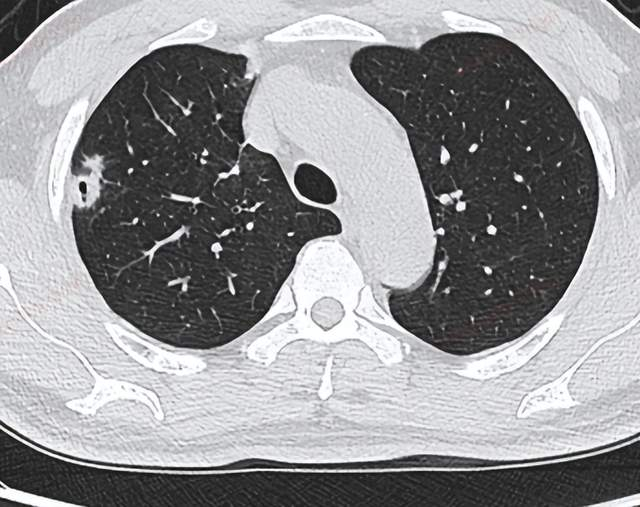

肺部结节患者行PET/CT发现肾脏肿瘤

男性,61岁

相关病史: 夜间盗汗,肺部结节性质待查,在安健康(检测)中心 接受PET/CT检查。

CT肺部扫图像

双肺散在多发结节,部分结节内见空洞形成。

PET/CT影像学表现

肺部结节广泛摄取,且左肾上极疑似环形代谢增高,与尿液摄取重叠,影像诊断。

大量饮水、排尿,反复多次,两小时后再次扫描:

PET/CT结论与病理结果对比

PET/CT结论:

左肾上极环形代谢增高影,CT未见异常密度,考虑肾癌,建议临床进一步检查。双肺多发类圆形结节、结片影,部分含空洞,代谢不同程度增高,考虑转移瘤。

肺部结节穿刺病理结果:

肺低分化肉瘤样癌,肾来源性。

对比结论:

PET-CT实现肿瘤的精准定位及确诊。